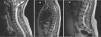

ResultadosSe encontraron un total de 167 casos de GGEI, incluyendo nuestro caso. En nuestra muestra, el 52% de los pacientes pertenece al sexo femenino, siendo la década de edad más afectada la que va de los 0 a los 9 años (35% de los pacientes). El déficit motor se establece como síntoma principal en pacientes adultos en mayor proporción que en pacientes pediátricos. Radiológicamente, este tumor se presenta con mayor hiperintensidad y captación de contraste que los astrocitomas y los ependimomas, así como un mayor porcentaje de quistes intratumorales. La mutación BRAFV600E es menos frecuente en los gangliogliomas espinales que en los supratentoriales. La cirugía con resección total es el tratamiento de elección. Solamente el 19% de los pacientes de la muestra recibieron radioterapia y solo el 9% quimioterapia como única vía de tratamiento.

ResultsA total of 167 cases of ISCGG were found, including our own. In our sample, 52% of patients were female and the most commonly affected age group was 0-9 years of age (35% of patients). Motor deficit has been found to be the main symptom in a larger proportion of adults patients versus pediatric patients. On X-ray, this tumor shows greater hyperintensity and contrast uptake than astrocytomas and ependymomas, as well as a higher percentage of intratumoral cysts. The BRAFV600E mutation is less common in spinal as opposed to supratentorial gangliogliomas. Surgery with complete resection is the treatment of choice. Only 19% of the patients in the sample received radiotherapy, and only 9% received chemotherapy as their only line of treatment.